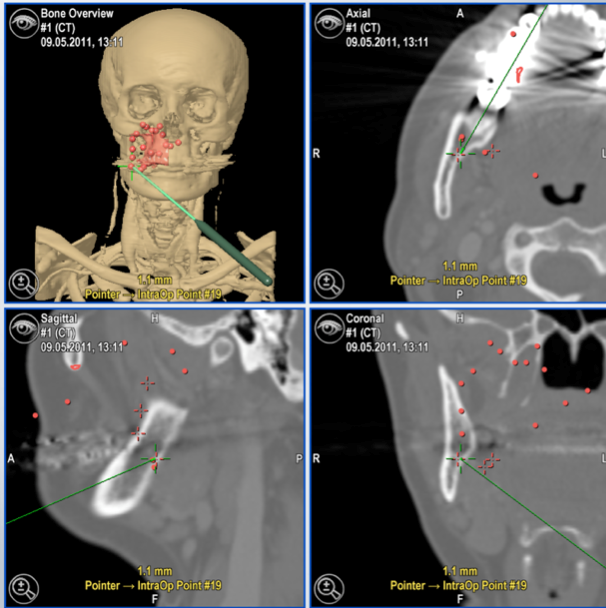

Im Rahmen einer Bestrahlungstherapie wird versucht, das verbleibende Tumorgewebe durch den Einsatz von ionisierenden Strahlen im Wachstum zu hindern. Gleichzeitig soll das benachbarte, gesunde Gewebe nicht beschädigt werden. Um nun ein Maximum der ionisierten Strahlen an den gewünschten Ort zu bekommen, ist es wichtig, dass der Tumor in seiner gesamten Ausdehnung erfasst und innerhalb des menschlichen Körpers markiert wird. Hier ergeben sich in der konventionellen Therapie die Probleme, dass durch die reduzierte Präzision der chirurgischen klinischen Informationen via OP-Bericht die Strahlenfelder prophylaktisch größer eingestellt werden. Auch wenn ein Tumor als nicht operabel eingestuft wird, benötigt der Strahlentherapeut eine genaue Lokalisation des Tumors innerhalb des Körpers, und zwar in seiner vollständigen dreidimensionalen Ausrichtung. Da die zur Verfügung stehenden bildgebenden Verfahren bisher nicht verändert oder markiert werden konnten, wird in unserer Forschungsgruppe an einem Workflow gearbeitet, bei dem die intraoperativ gesammelte Tumorwolke im präoperativen Datensatz hinterlegt wird. Nach Eingang des histologischen Befundes werden die virtuellen Punkte in Abhängigkeit vom histologischen Befund farblich markiert. Auch die virtuellen Punkte, die nicht am berechneten Sicherheitsabstand liegen, werden entsprechend farblich markiert. Das bedeutet, dass der Strahlentherapeut durch einfache Modifikationen im Datensatz erkennen kann, welche Punkte den vermeintlichen Resttumor anzeigen, welche Punkte einen zu kleinen Sicherheitsabstand markieren und welche Punkte frei von Tumorgewebe sind.